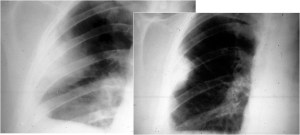

SIGNO DE LA AUSENCIA DE PARED SUPERIOR

Cuando en una radiografía de tórax se ve un nivel hidraéreo hay que establecer la diferencia entre intrapulmonar (absceso, quiste, tumor cavitado) o extrapulmonar (derrame encapsulado, empiema). La ausencia de la pared superior de una colección intratorácica con nivel hidroaéreo, en al menos una de las dos proyecciones de tórax, es un signo que permite diferenciar el encapsulado pleural de cavidades de localización intrapulmonar.

En las imágenes vemos un nivel hidroaéreo en hemitórax derecho (flechas rojas) sin que sea visible la pared de la cavidad. Se trata por tanto de una colección extrapulmonar.

Estos esquemas permiten entender el significado del signo. Las colecciones intrapulmonares (izquierda) suelen tener una morfología redondeada, ya que están rodeadas por entero de pulmón y la resistencia de este al crecimiento de la colección es igual en todos sus puntos. Por ello, en las dos proyecciones los bordes superiores de la cavidad -delimitados por el aire que contiene la misma- son perpendiculares a la incidencia del rayo, y por tanto son visibles.

Las colecciones extrapulmonares (derecha) tienen a crecer limitadas por la pleura, que ofrece resistencia al crecimiento de la colección. Así, estas colecciones tienen una forma alargada (en «huso») a lo largo del espacio extrapulmonar. Por ello, en al menos una de las proyecciones, los bordes de la cavidad no son perperdiculares a la incidencia del rayo, y por tanto no son visibles. Como muestra el esquema, las colecciones posteriores (y también las anteriores, se ven bien en la proyección lateral y falta la pared superior en la proyección PA. Con las colecciones laterales ocurre lo contrario.